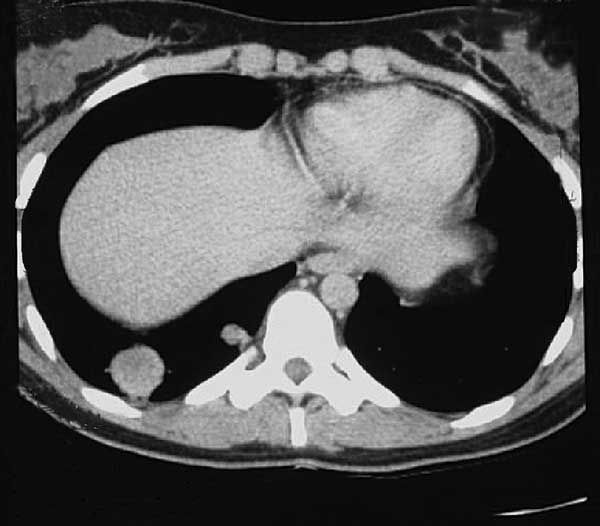

However, a CT scan of the chest displayed 2 right upper lobe nodules about 2 cm and 1 cm in diameter (Figure 1). The rest of the lung parenchyma and vasculature and the mediastinum were normal. The results of a CT-guided fine-needle aspiration biopsy of the lung lesions were nondiagnostic. Bacterial and fungal cultures were negative for organisms.

Figure 1 – Two discrete nodules are demonstrated in the right upper lung parenchyma on this CT scan.